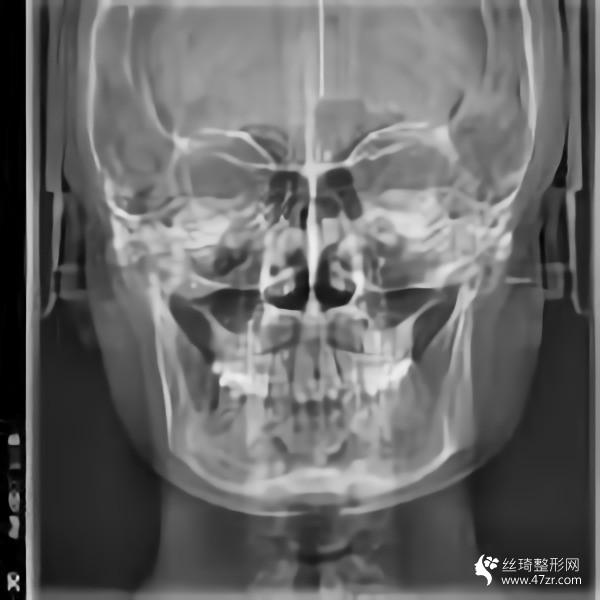

金柱翰院長韓國頜面整形專家、韓國鼻整形專家、下頜角截骨術(shù)技術(shù)專家、韓國“微整形技術(shù)研究”專家,多次接受記者采訪,南京醫(yī)科大學(xué)國際整形教學(xué)研究中心副主任,南京醫(yī)科大學(xué)友誼整形醫(yī)院專家委員會(huì)常委;擅長鼻整形手術(shù):自體鼻中隔軟骨移植隆鼻,耳軟骨移植隆鼻,肋骨移植隆鼻,假體隆鼻,鼻尖鼻翼整形手術(shù),各種畸形鼻的矯正,隆鼻失敗的修復(fù),歪鼻的矯正;

從高中開始,人們就一直說我的臉很方。就算不直接說臉,我也會(huì)說臉很大。每次聽到心里都很無奈,臉上都在埋怨我...每次我回嘴的時(shí)候,也是一副滿不在乎的表情。然而,我的心還是不自覺地開始關(guān)心它。說白了,我要小一點(diǎn)的臉。其實(shí)我一直有做下頜角的想法。之前我還在讀書,沒錢?,F(xiàn)在出來工作了,經(jīng)濟(jì)獨(dú)立了,咨詢了醫(yī)院說可以,終于可以解決這個(gè)大面子問題了

手術(shù)后15天。過來拆線。反正我覺得我更喜歡自己。一點(diǎn)都好看。看起來很可愛。目前有點(diǎn)腫,但輪廓線條開始慢慢顯現(xiàn)。畢竟拆線。恢復(fù)狀態(tài)還是很滿意的。目前較重要的是照顧好自己。父母不在身邊。我還沒有過恢復(fù)期。我不能吃得太隨便。我必須注意我的飲食。這個(gè)真的是先苦后甜。不過為了后面的恢復(fù)果,一切都是值得的

回來快一個(gè)月了,基本沒有腫脹,輪廓清晰柔和。不知道是不是錯(cuò)覺,感覺皮膚細(xì)膩多了。哈哈,雖然有美顏加持,但是大家看不出來很正常,但是可以自己感受一下。院長的技術(shù)真的很好,不愧是變臉王。剛來的時(shí)候看到幾個(gè)美女好像是花錢磨骨頭的,表現(xiàn)的多火啊。合格的醫(yī)生就是不一樣,讓人安心。醫(yī)院里的人手術(shù)后一直在回來康復(fù)。說起來有點(diǎn)太熱情了,讓我不敢接電話。

我又來了。我不記得上次是多久了。年紀(jì)大了記憶力下降了很多,但身邊認(rèn)識(shí)的很多人也會(huì)這樣。好像沒有明X的辦法。再說說我的下頜角手術(shù)。雖然手術(shù)的時(shí)候感覺不深,但是手術(shù)后確實(shí)記得很深,總是需要經(jīng)歷一些徹骨的寒冷,梅花才會(huì)有香味。較近的照片給你們發(fā)一波,如果手術(shù)做的好那么你以后就不會(huì)后悔了。

在生活中,我們往往忘記了健康和鍛煉,大多數(shù)人會(huì)在自己的世界里沉默,但生活中的許多實(shí)際問題仍然會(huì)把你拉回現(xiàn)實(shí)。我其實(shí)很喜歡去健身房,但是是時(shí)間問題導(dǎo)致我沒能得到我想要的。另外,我在下頜角休息了很久,臉部好了很多,運(yùn)動(dòng)還是不可或缺的。其實(shí)我覺得健康較重要,其次是外表和對(duì)自己的信任,哈哈